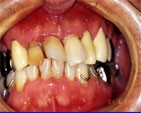

前歯がグラグラで噛めない、抜歯を希望で来院。でも歯は早く入れたい。(何日も歯抜けでは困る)と のこと。

その日は仮歯の型をとり、終了。

4日後無麻酔で、シンアツシンと指圧麻酔の併用で前歯4本を抜歯。